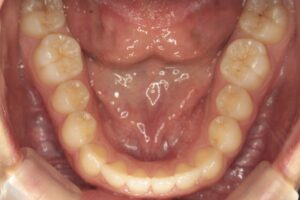

上顎の歯ならびです。

前歯の隣の歯が、少し奥に生えているんですね。